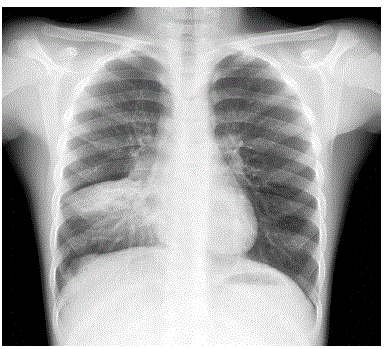

Adolescente masculino, 13 anos de idade, portador de anemia falciforme em seguimento regular com hematologista, apresenta queixa de febre e tosse há dois dias e dor em face anterior do tórax a direta. Ao exame clínico encontra-se em regular estado geral, levemente descorado, FC: 84 bpm, FR: 34 ipm, Saturação de Oxigênio: 95% em ar ambiente, Temp: 38°C, PA: 100/60 mmHg. Realizou radiografia de tórax, que mostrou a imagem abaixo:

Radiografia de tórax realizada há 15 minutos: